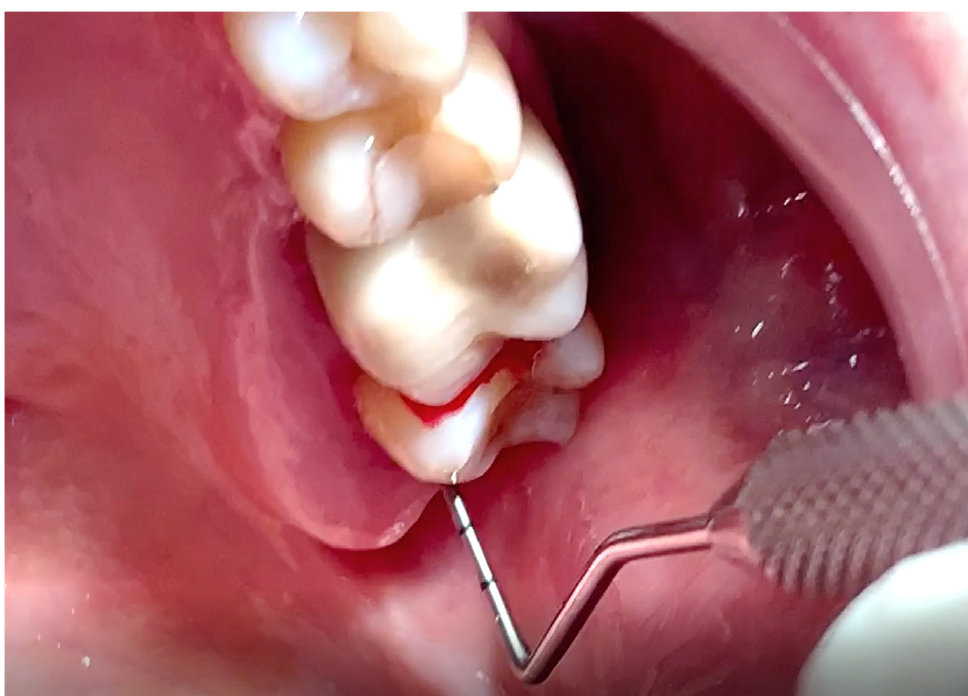

На первостепенном уровне проведена запись клинических данных («золотой стандарт»). Затем выполнена визуальная диагностика с помощью стоматологического зеркала, особо внимание уделяли скоплению зубного налета, выявление рецессии десны (рис. 3). Клинический осмотр на каждом этапе включал измерение глубины зондирования кармана и потери прикрепления (рис. 4). Сила зондирования составляла 0,20 Н, что соответствует 25 г.

До начала проведения подготовки зубодесневого комплекса у пациентов с низкой коронкой опорных зубов была определена гигиена полости рта, на основании показателей которых выполнена профессиональная чистка зубов. Так, API составил 69 %, индекс сосочковой кровоточивости PBI – 28 %, CPITN – (2,1 ± 0,3) балла. При зондировании зубодесневой борозды глубина погружения определена в (2,7 ± 0,2) мм. Далее пациентам согласно рандомизации выполнена одна из методик подготовки зубодесневого комплекса к ортопедическому лечению – гингивэктомия, гингиворетракция и гингивопластика (рис. 5). Спустя 14 дней при оценке клинических показателей были получены следующие значения (табл. 1).

Рис. 5. Наложение швов после выполнения гингивопластики